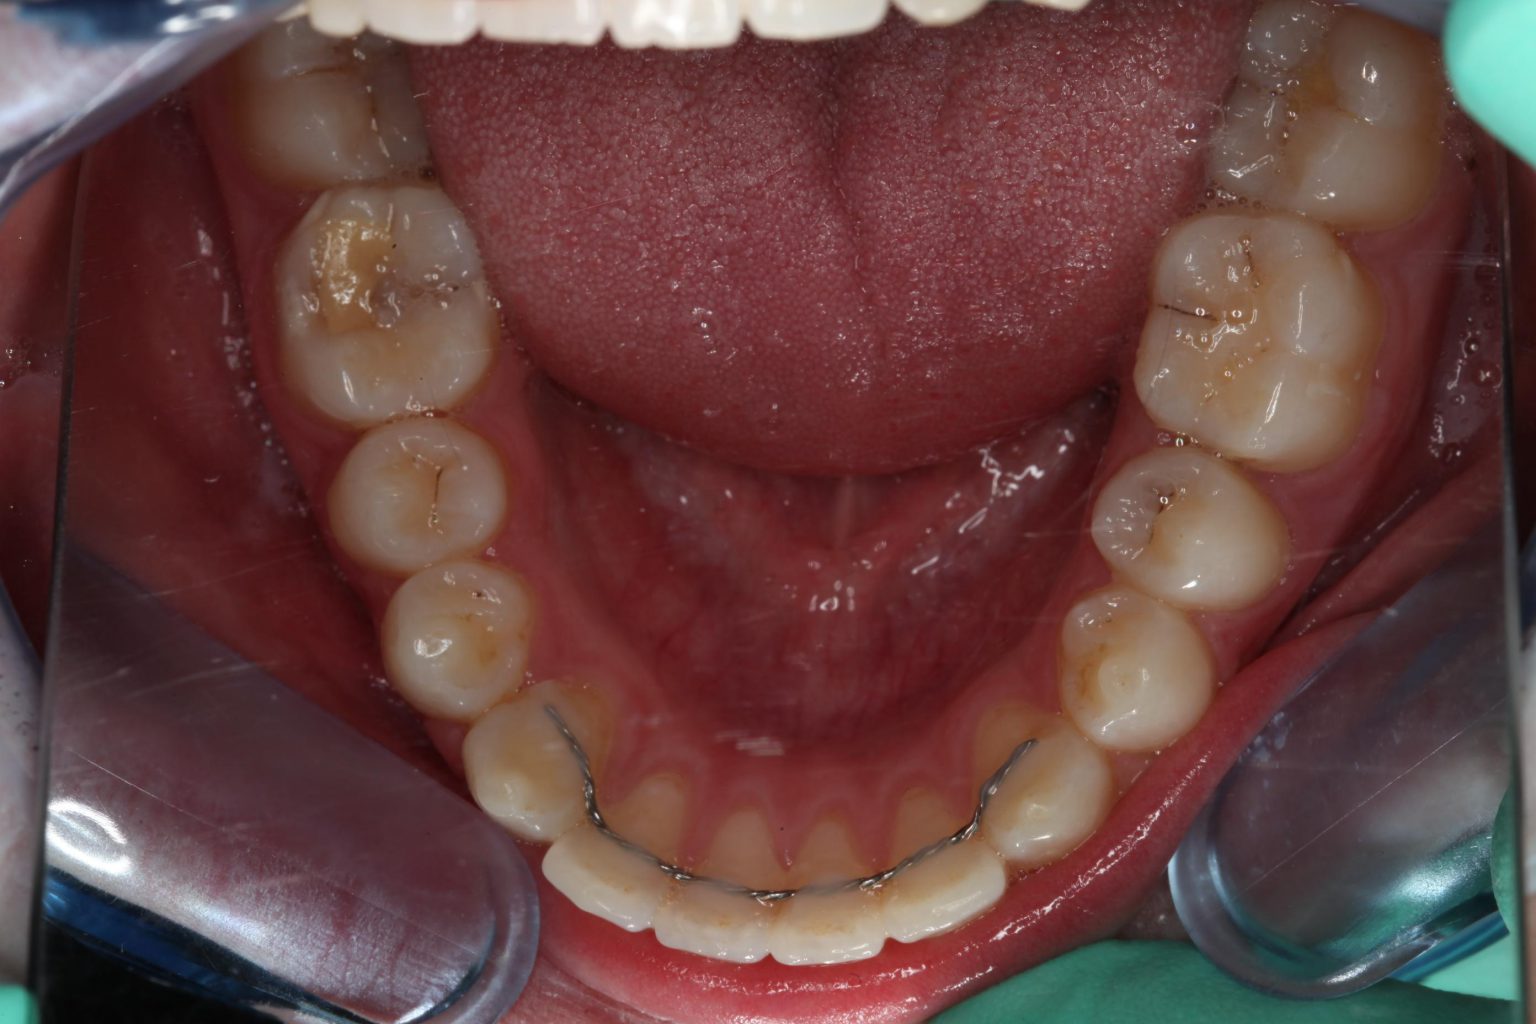

Aan de wat dikkere achterkant kun je zien dat deze nieuwe voortand eigenlijk een kiesje is. Rechts zie je nog de open plek waar het kiesje vandaan gekomen is.

De beugel gaat die plek nog dicht trekken.

Je ziet dat nog aan de binnenkant, omdat je daar het knobbeltje van het kiesje nog ziet. Op deze foto zie je ook de al bijna dicht-geschoven plekken waar die kiesjes vandaan geopereerd werden, meer achter in de mond.